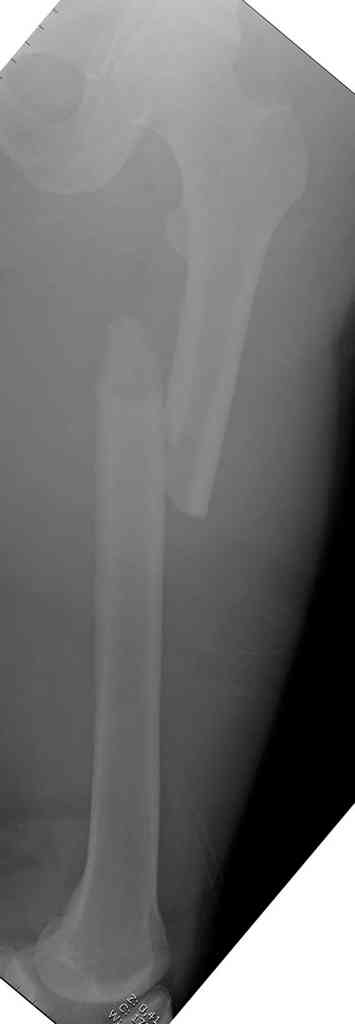

Здесь представлены снимки больного 65 лет, поступившего с диагнозом перелом

бедра после автоаварии.

В первый же день произведено антеградное штифтованием DePuy Trochanteric Nail.

На второй день (7) обнаружен пропущенный перелом,